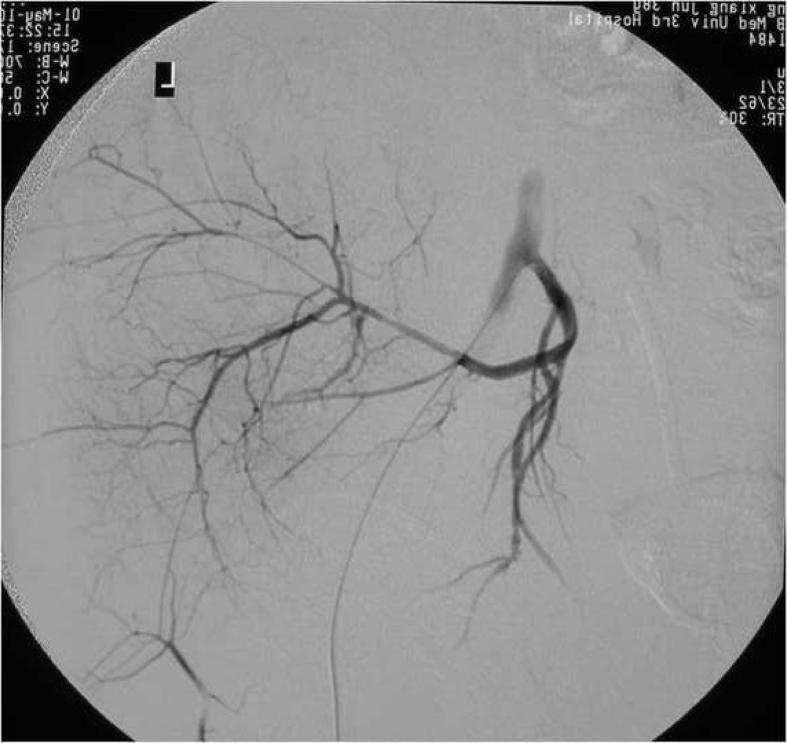

成年患者骶髂关节前脱位后隐匿性髂外静脉损伤

Occult external iliac vein injury after anterior dislocation of the sacroiliac joint in adult patient.

Anterior dislocation of the sacroiliac joint, characterized by dislocation of the ilium anterior to the sacrum, is a subtype of complete posterior pelvic ring disruption. This injury occurs mostly in children. We present an adult patient with anterior dislocation of the sacroiliac joint. It was associated with numerous complications. To the best of our knowledge, it is only the second case reported in the literature.

摘要